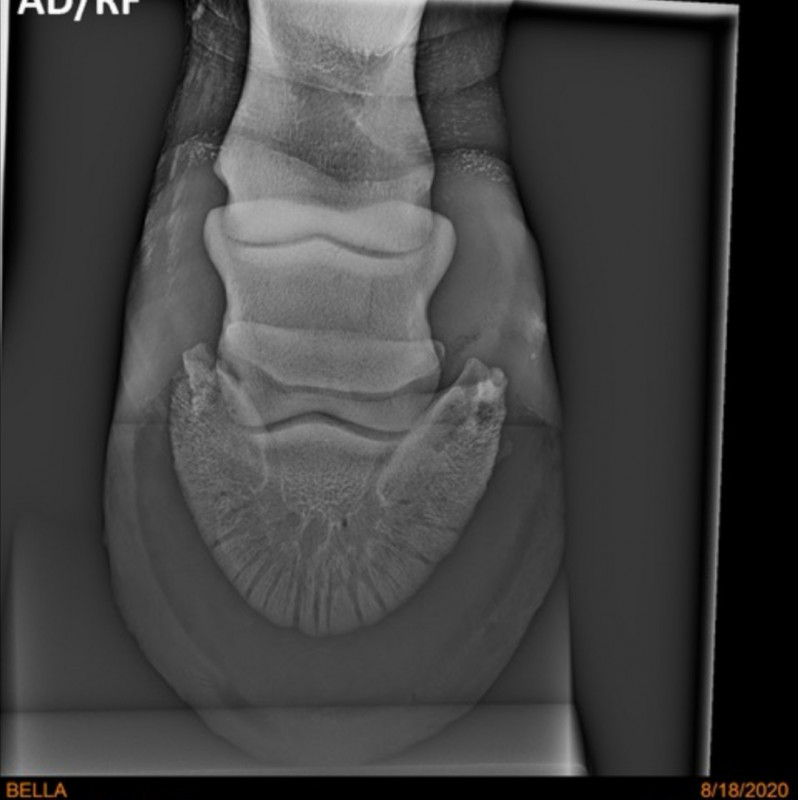

Je poste les radios qui avaient été faites quand même. La veto n'avait rien vu mais au cas où...